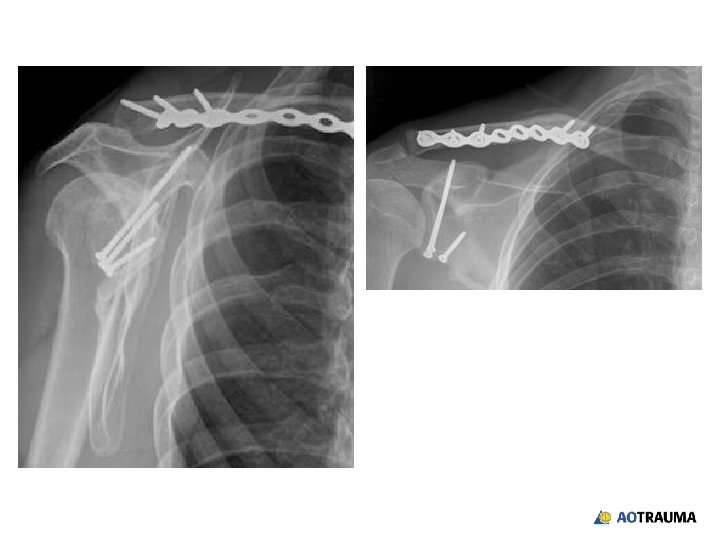

Intraoperative x-ray

Reinjury of right shoulder Patient lifted son weighing 25 kg 2 weeks postoperatively, new bump